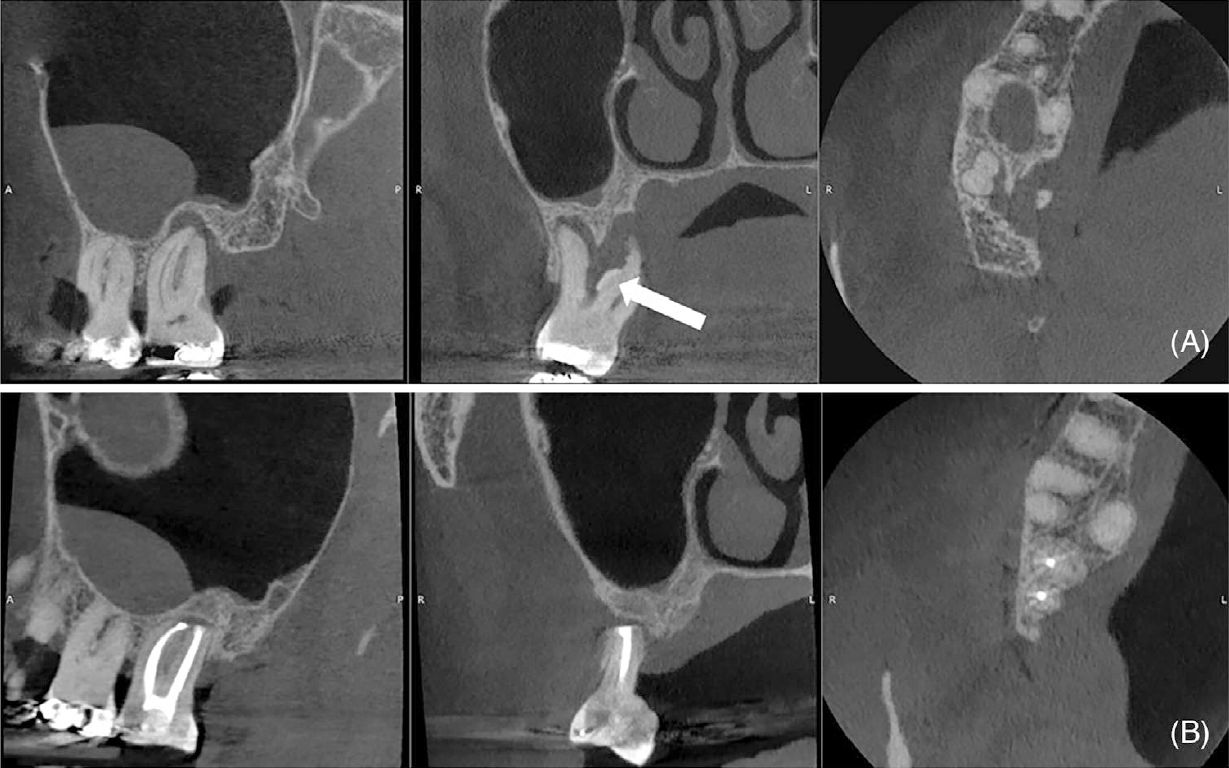

Фото 2. (A) Исходное КТ зуба 17 (сагиттальная, корональная и аксиальная проекции), демонстрирующее крупный участок сниженной плотности костной ткани, зубной камень (стрелка), кариес в области фуркации и сохранённую щёчную кортикальную пластинку. (B) КТ через 14 месяцев после операции (сагиттальная, корональная и аксиальная проекции), демонстрирующее образование кости на дистальной поверхности зуба 17 и ремоделирование апикальной и небной областей зуба 16. Линия, пониженной плотности, наблюдаемая в апикальной трети щёчных корней, соответствует репаративной ткани (коллагенизация)

Фото 5. (A) Исходное КТ (сагиттальная, корональная и аксиальная проекции), демонстрирующее очаг пониженной плотности вокруг зубов 16 и 15, фенестрацию щёчной кортикальной пластинки и утолщение слизистой оболочки верхнечелюстной пазухи. (B) КТ через 10 месяцев после операции (сагиттальная, корональная и аксиальная проекции), демонстрирующее образование кости, апикальное ремоделирование зуба 15, сохранение объёма тканей и нормализацию состояния слизистой оболочки верхнечелюстной пазухи